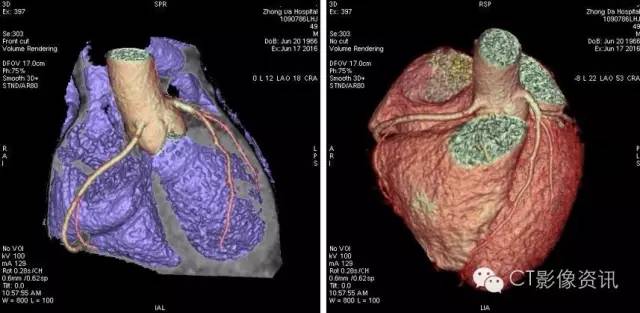

病例2:男性,49岁,BMI值26.4,冠状动脉CT成像与心肌灌注检查,只需一次打药,Revolution即可完成形态学和功能学检查。

CCTA及血管分析如下: